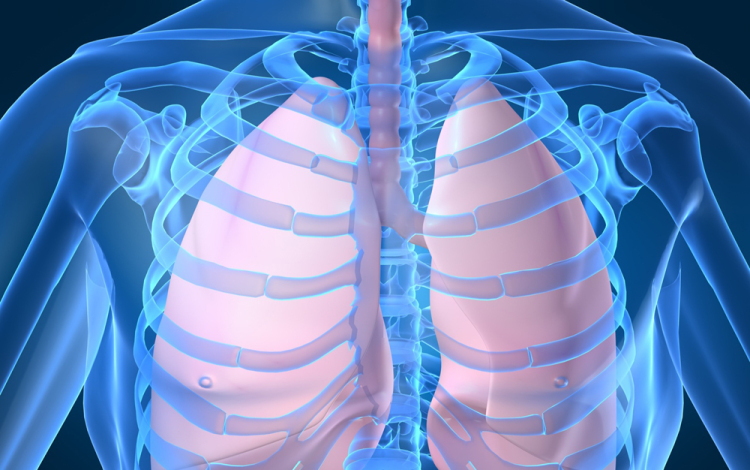

Húszan várnak tüdőátültetésre Magyarországon

Húszan várnak tüdő-transzplantációra az országban, tavaly 12 magyar betegen hajtottak végre ilyen szervátültetést külföldön

- mondta Kásler Miklós, az Országos Onkológiai Intézet főigazgatója vasárnap az M1 aktuális csatorna esti műsorában. A főigazgató ezt azzal kapcsolatban közölte, hogy még idén elvégezhetik az első tüdőátültetést Magyarországon.

Magyarországról tavaly 37 tüdőt szállítottak Bécsbe átültetési céllal; ha nálunk is elérhetővé válik a műtét, akkor várhatóan a környező országokból is Budapestre érkezik majd a betegek egy része Bécs helyett - mondta a főigazgató.